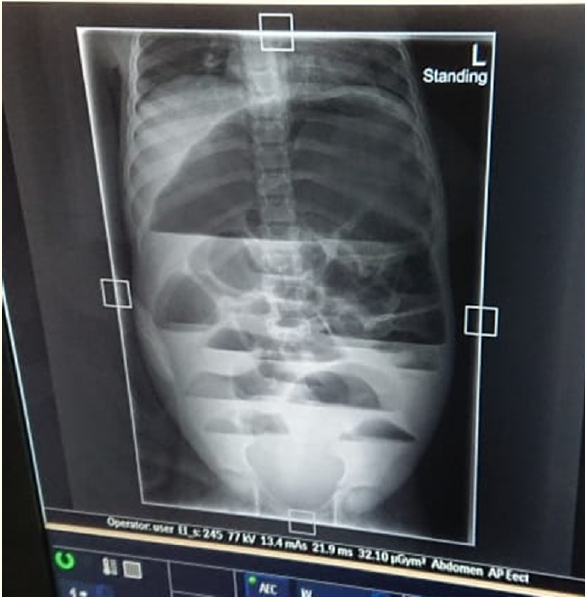

Case Report

Midgut Malrotation- A Case of a 11-Year-Old Girl

Amos Mailosi and Modai Clement Mnenula. 4(11): 32-36.